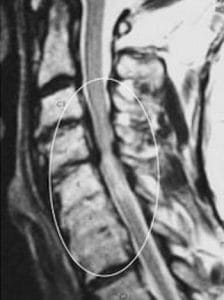

Ver caso real de tratamiento del CCE por laminoplastía.

El diagnóstico de la estenosis del canal cervical se basa en la utilización de técnicas de imagen avanzadas. La resonancia magnética (RM) emerge como la herramienta primordial para visualizar con detalle las estructuras nerviosas, discernir la presencia de compresión y evaluar posibles factores contribuyentes, como hernias discales o cambios degenerativos.